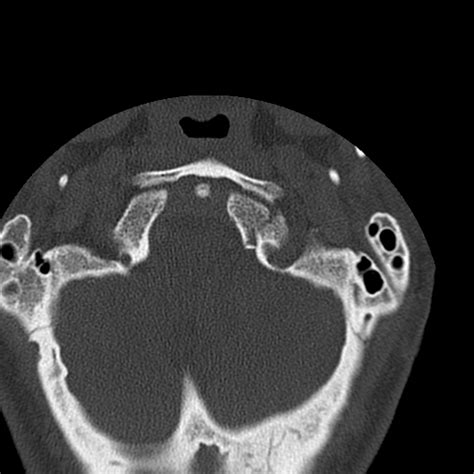

• Computed Tomography (CT) Scan: This is the gold standard for diagnosing occipital condyle fractures. CT scans provide detailed images of the bony structures and can help identify the location and extent of the fracture.

Occipital condyle fractures are classified based on their pattern and mechanism of injury. The most commonly used classification system is the Anderson and Montesano classification, which categorizes these fractures into three types:

Type I Compression fracture of the occipital condyle Axial loading with compression